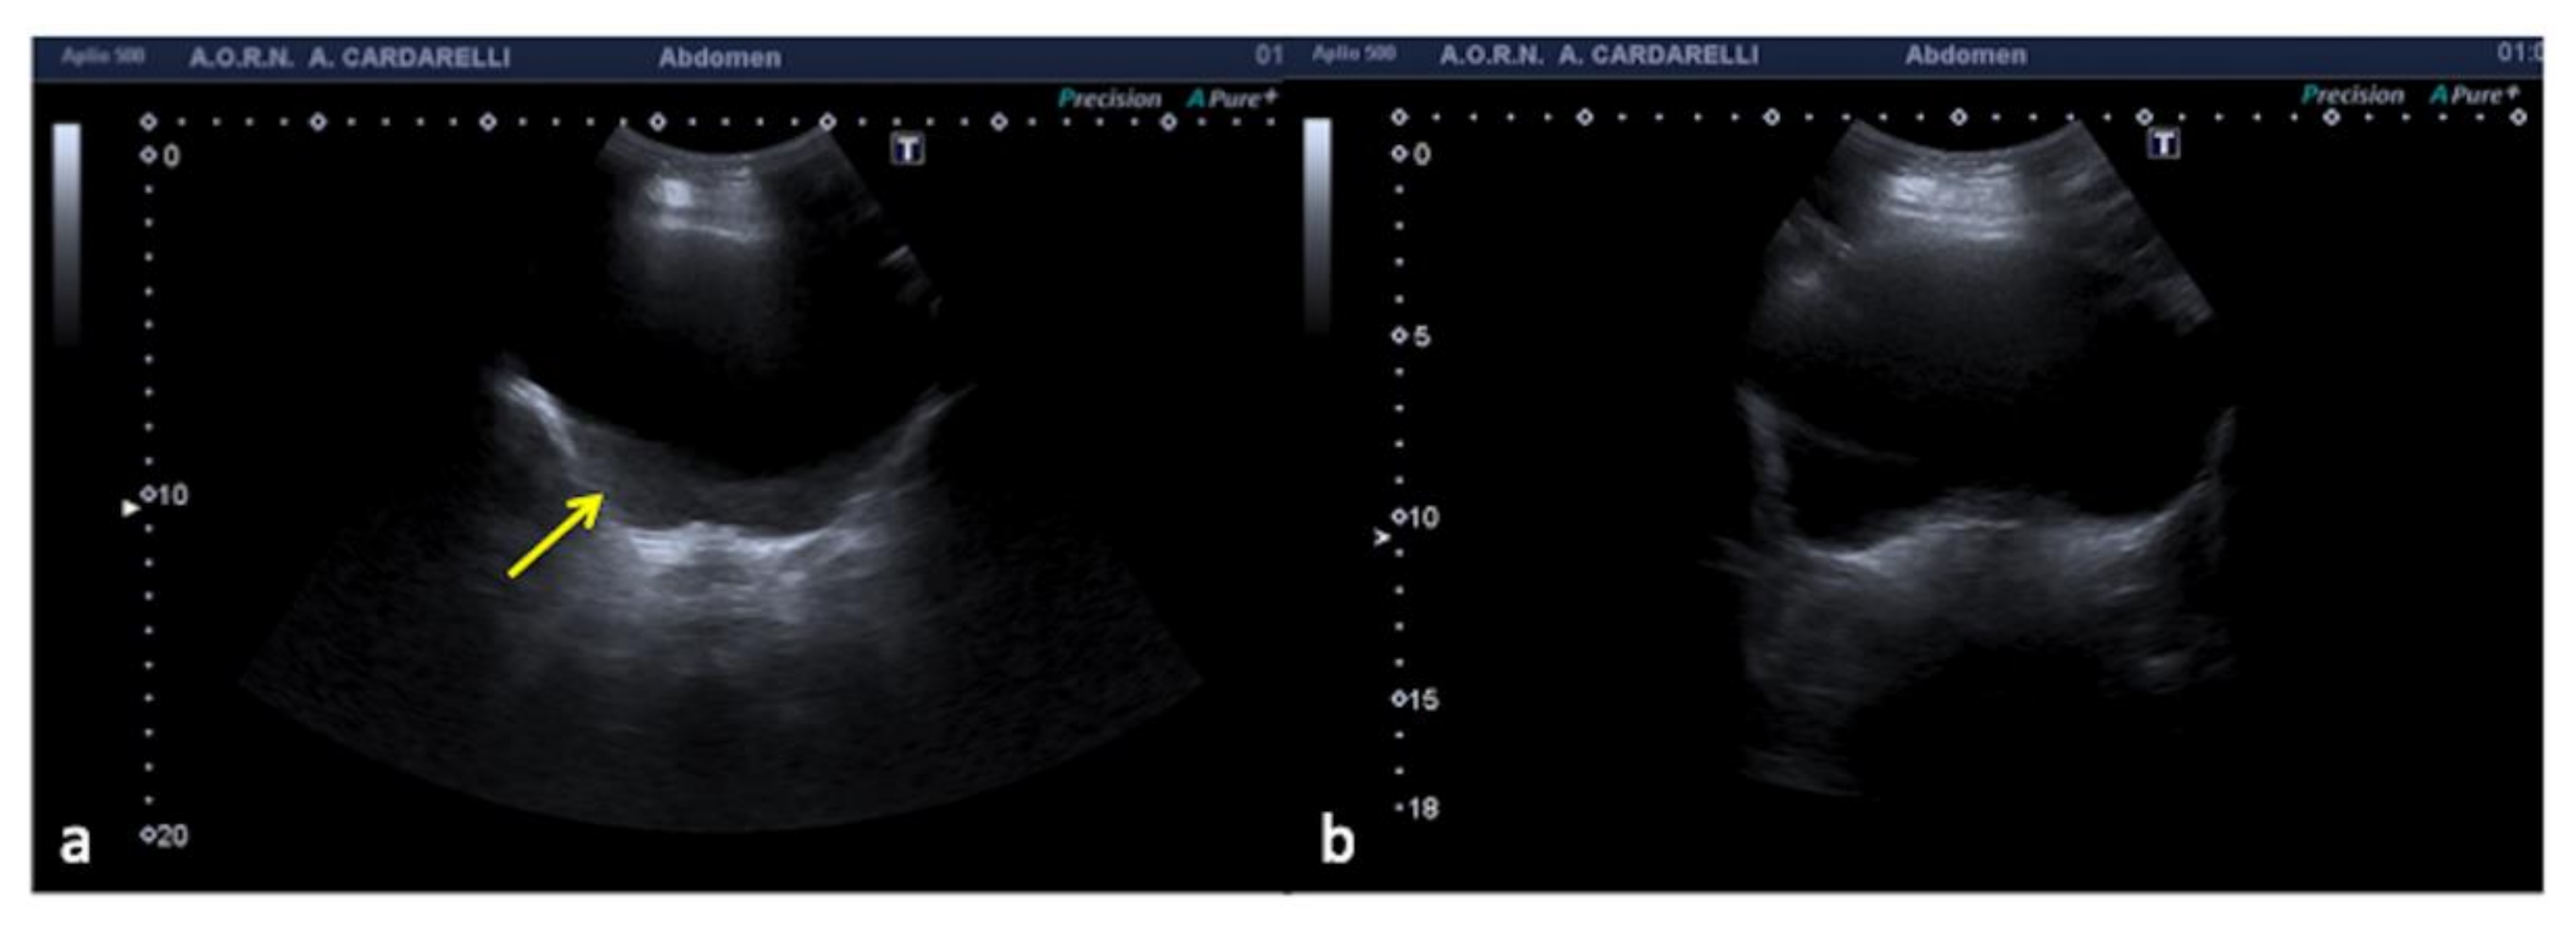

3.1.2. The Mirror-Imaging Effect